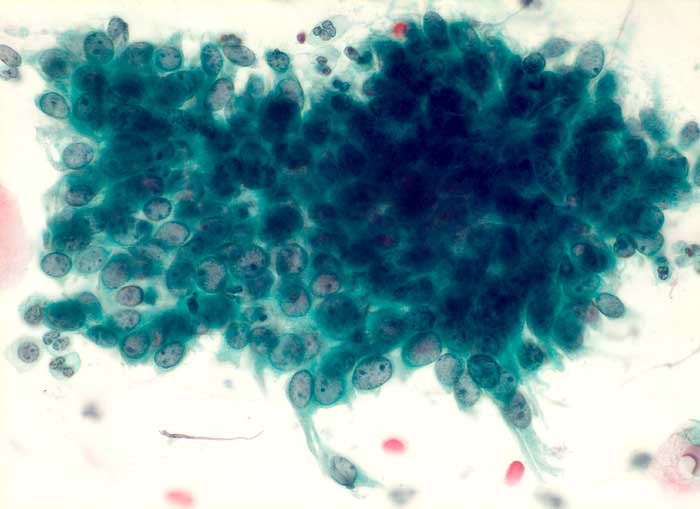

PathoPic – image database / PathoPic ID 6076 - regeneratorische Veränderungen des Zylinderepithels

regeneratorische Veränderungen des Zylinderepithels

Portioabstrich: Zylinderepithelien mit vergrösserten Kernen und hoher Kern-Plasma Relation. Grosse Nukleolen. Vesikuläre Kerne mit feinem Chromatin und regelmässiger Kernmembran. Die Zellen sind in regelmässigen Abständen voneinander gelagert.

Die DNA-Hybridisierung zum Nachweis von HPV-Sequenzen ergab:

HPV Typ low grade (6/11/42/43/44) negativ. HPV Typ high grade (16/18/31/33/35/45/51/52/56) negativ.